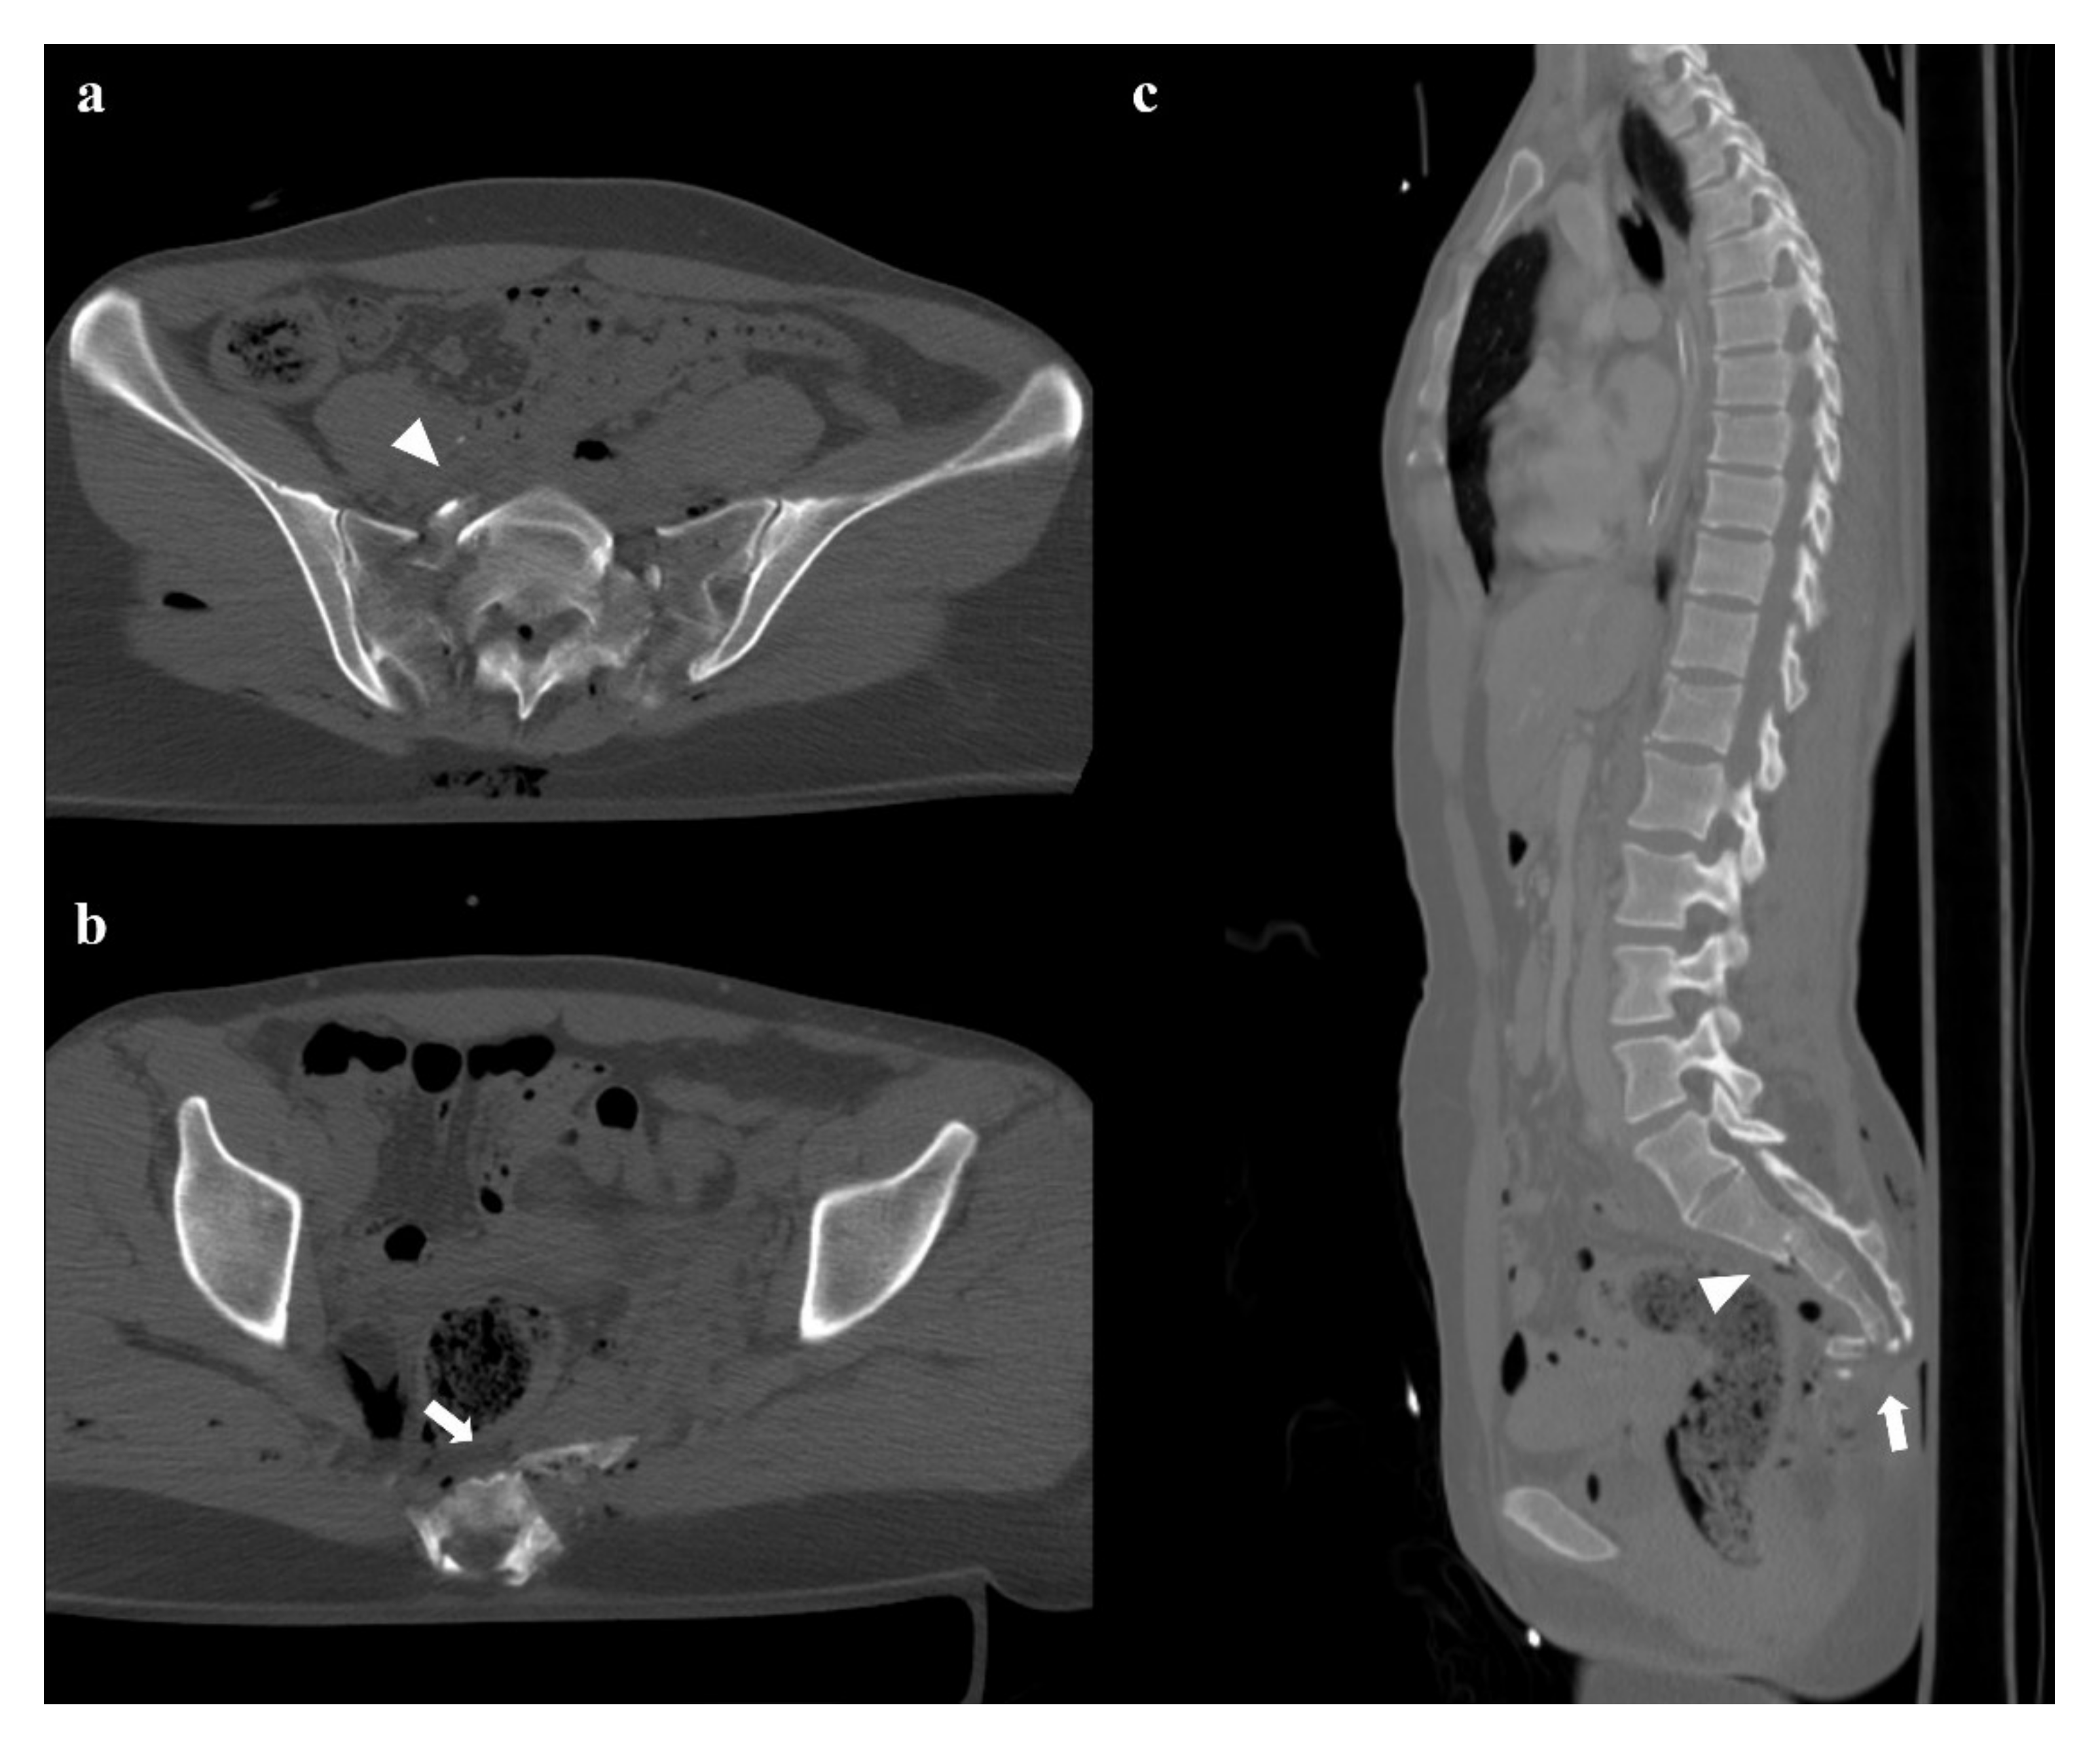

A force vector acting in the craniocaudal direction (typically, a fall from a height) can cause a destruction of the posterior elements of the pelvis and a cranial shift of the hemipelvis [13]. Involvement of the posterior arch of the pelvic ring is characterized by the avulsion of the transverse process of the fifth lumbar vertebra on the impact side, which is a sign of iliolumbar ligament rupture (Figure 7). Along the posterior arch, vertical shear injuries can also cause vertical fracture of the sacrum, sacroiliac diastasis, and iliac wing fracture. Anteriorly, this kind of trauma may show a disruption of the pubic symphysis and vertical fracture of the pubic rami. Rotational and vertical instability is the result of vertical shear injuries, that are also associated with vascular, genitourinary, and neurological complications [14]. Vertical shear injuries require a surgical fixation [3].

Figure 7. Vertical shear fracture. Axial CT images show avulsion of the left transverse process of the fifth lumbar vertebra (black arrow in (a)), fracture of the left side of the sacrum with involvement of the foraminal zone (black arrowhead in (b)), and fracture of the right superior and inferior pubic branches (white arrows in (c,d)). There is also a little fracture of the right wing of the sacrum, and a posterior widening of the right sacroiliac joint (white arrowheads in (b)). Three-dimensional volume-rendering CT reconstruction clearly depicts the instability of the pelvic ring, with the fracture of the left transverse process of the fifth lumbar vertebra and the cranial shift of the left hemipelvis (e).